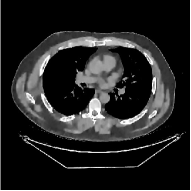

This section compares the reconstruction quality and runtime among the proposed MBIR method, PWLS-ST-, and other three MBIR methods, PWLS-EP, PWLS-DL, and PWLS-ST-. Table I shows that, for both 2D and 3D sparse-view CT reconstructions of the XCAT phantom, the proposed PWLS-ST- model outperforms PWLS-EP and PWLS-ST- in terms of RMSE. In addition, PWLS-ST- using a square transform (of size ) achieves lower RMSE than PWLS-DL using an overcomplete dictionary (of size ) for 2D sparse-view reconstructions. Fig. 3(a) and Fig. 4 show the reconstructed images for 2D and 3D phantom experiments, with different reconstruction models and different number of views. (See the corresponding error maps in the supplement.) The proposed PWLS-ST- consistently gives more accurate image reconstructions compared to other MBIR methods. Specifically, PWLS-ST- has smaller errors in the heart region (see zoom-ins in Fig. 3(a)) of 2D reconstructions than PWLS-DL and PWLS-ST-. In addition, compared to PWLS-ST-, PWLS-DL and PWLS-ST- have some ringing artifacts around the edges with high transition, e.g., edges between air and soft tissues. (See a comparison of profiles of PWLS-ST- and PWLS-ST- in the supplement.) In particular, PWLS-ST- and PWLS-DL give more visible ringing artifacts for 2D reconstruction from fewer views, and PWLS-ST- has these ringing artifacts for 3D reconstructions regardless of the number of views (see zoom-ins in Fig. 4). Table II reports runtimes of different MBIR methods in reconstructing the -views XCAT phantom scan. (FBPConvNet is a non-MBIR method and its runtime for processing a image is approximately one second with a TITAN Xp GPU.) While providing better reconstruction quality, the proposed Algorithm 1 of PWLS-ST- has shorter runtime compared to the algorithms of PWLS-DL and PWLS-ST- in Section III-A. Similar to the PWLS-EP algorithm, the reconstruction time of the PWLS-DL, PWLS-ST-, and PWLS-ST- algorithms can be further reduced by using ordered subsets [51].

Fig. 3(b) shows that when tested on the clinical scan data, the proposed PWLS-ST- method improves reconstruction quality in terms of noise and artifacts removal (e.g., see zoom-ins for soft-issue regions), and edge preservation (e.g., see zoom-ins for bone regions), compared to PWLS-EP and PWLS-ST-. Compared to PWLS-DL, PWLS-ST- achieves comparable image quality, but requires less computational complexity.

The benefit of the proposed PWLS-ST- over PWLS-ST- can be explained when there exist some outliers for some : in (12) gives equal emphasis to all sparse codes – from small to large coefficients that generally correspond to edges in low- and high-contrast regions, respectively – in estimating ; however, PWLS-ST- adjusts to mainly minimize the outliers, i.e., it may not pay enough attention to reconstruct regions with small coefficients. The histogram results in Fig. 1 reveal model mismatch of PWLS-ST- over the iterations. Fig. 3, Fig. 4, and Table I show that PWLS-ST- can moderate model mismatch, and provides more accurate reconstruction than PWLS-ST-.

| (a) 2D fan-beam CT experiments |